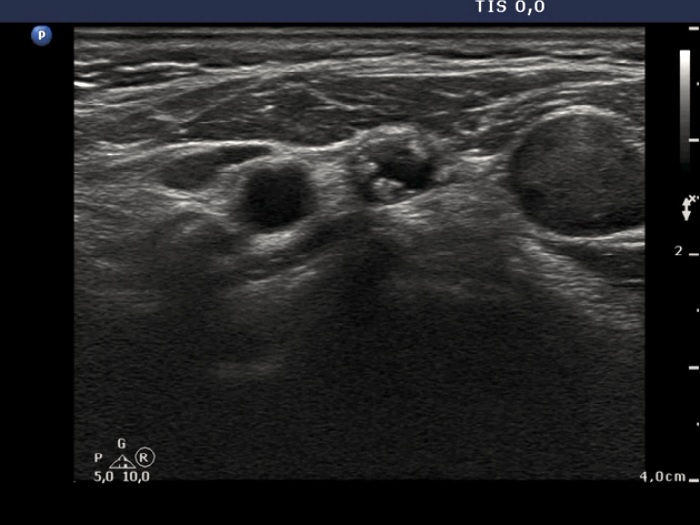

Medullary carcinoma (histological diagnosis) - case 617

Right thyroid lobe

A metastatic lymph node in the right side of the neck

There are similar hyperechogenic figures in the primary and metastatic focus. These are multiple, have an irregular shape and vary greatly in size.